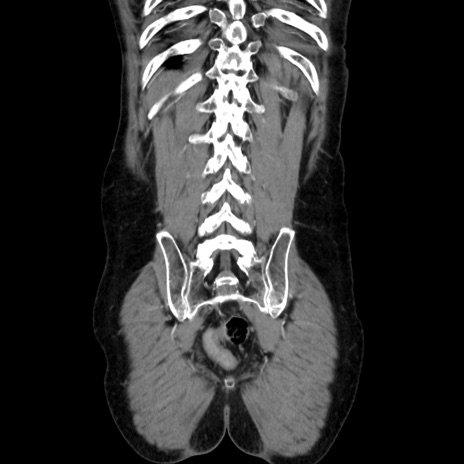

症例37(冠状断像)

【症例】40歳代 男性

【主訴】腹痛

【現病歴】4時間ほど前に電車に乗車中に臍部上より腹痛出現。徐々に増悪し起立困難となり、救急外来受診。生ものは数日食べていない。今朝お雑煮を食べた。

【身体所見】BT 36.8℃、BP 117/84mmHg、HR 91/min、SpO2 97%、苦悶様、腹部:臍上部広範囲圧痛あり、反跳痛±

【データ】WBC 8100、CRP 0.03